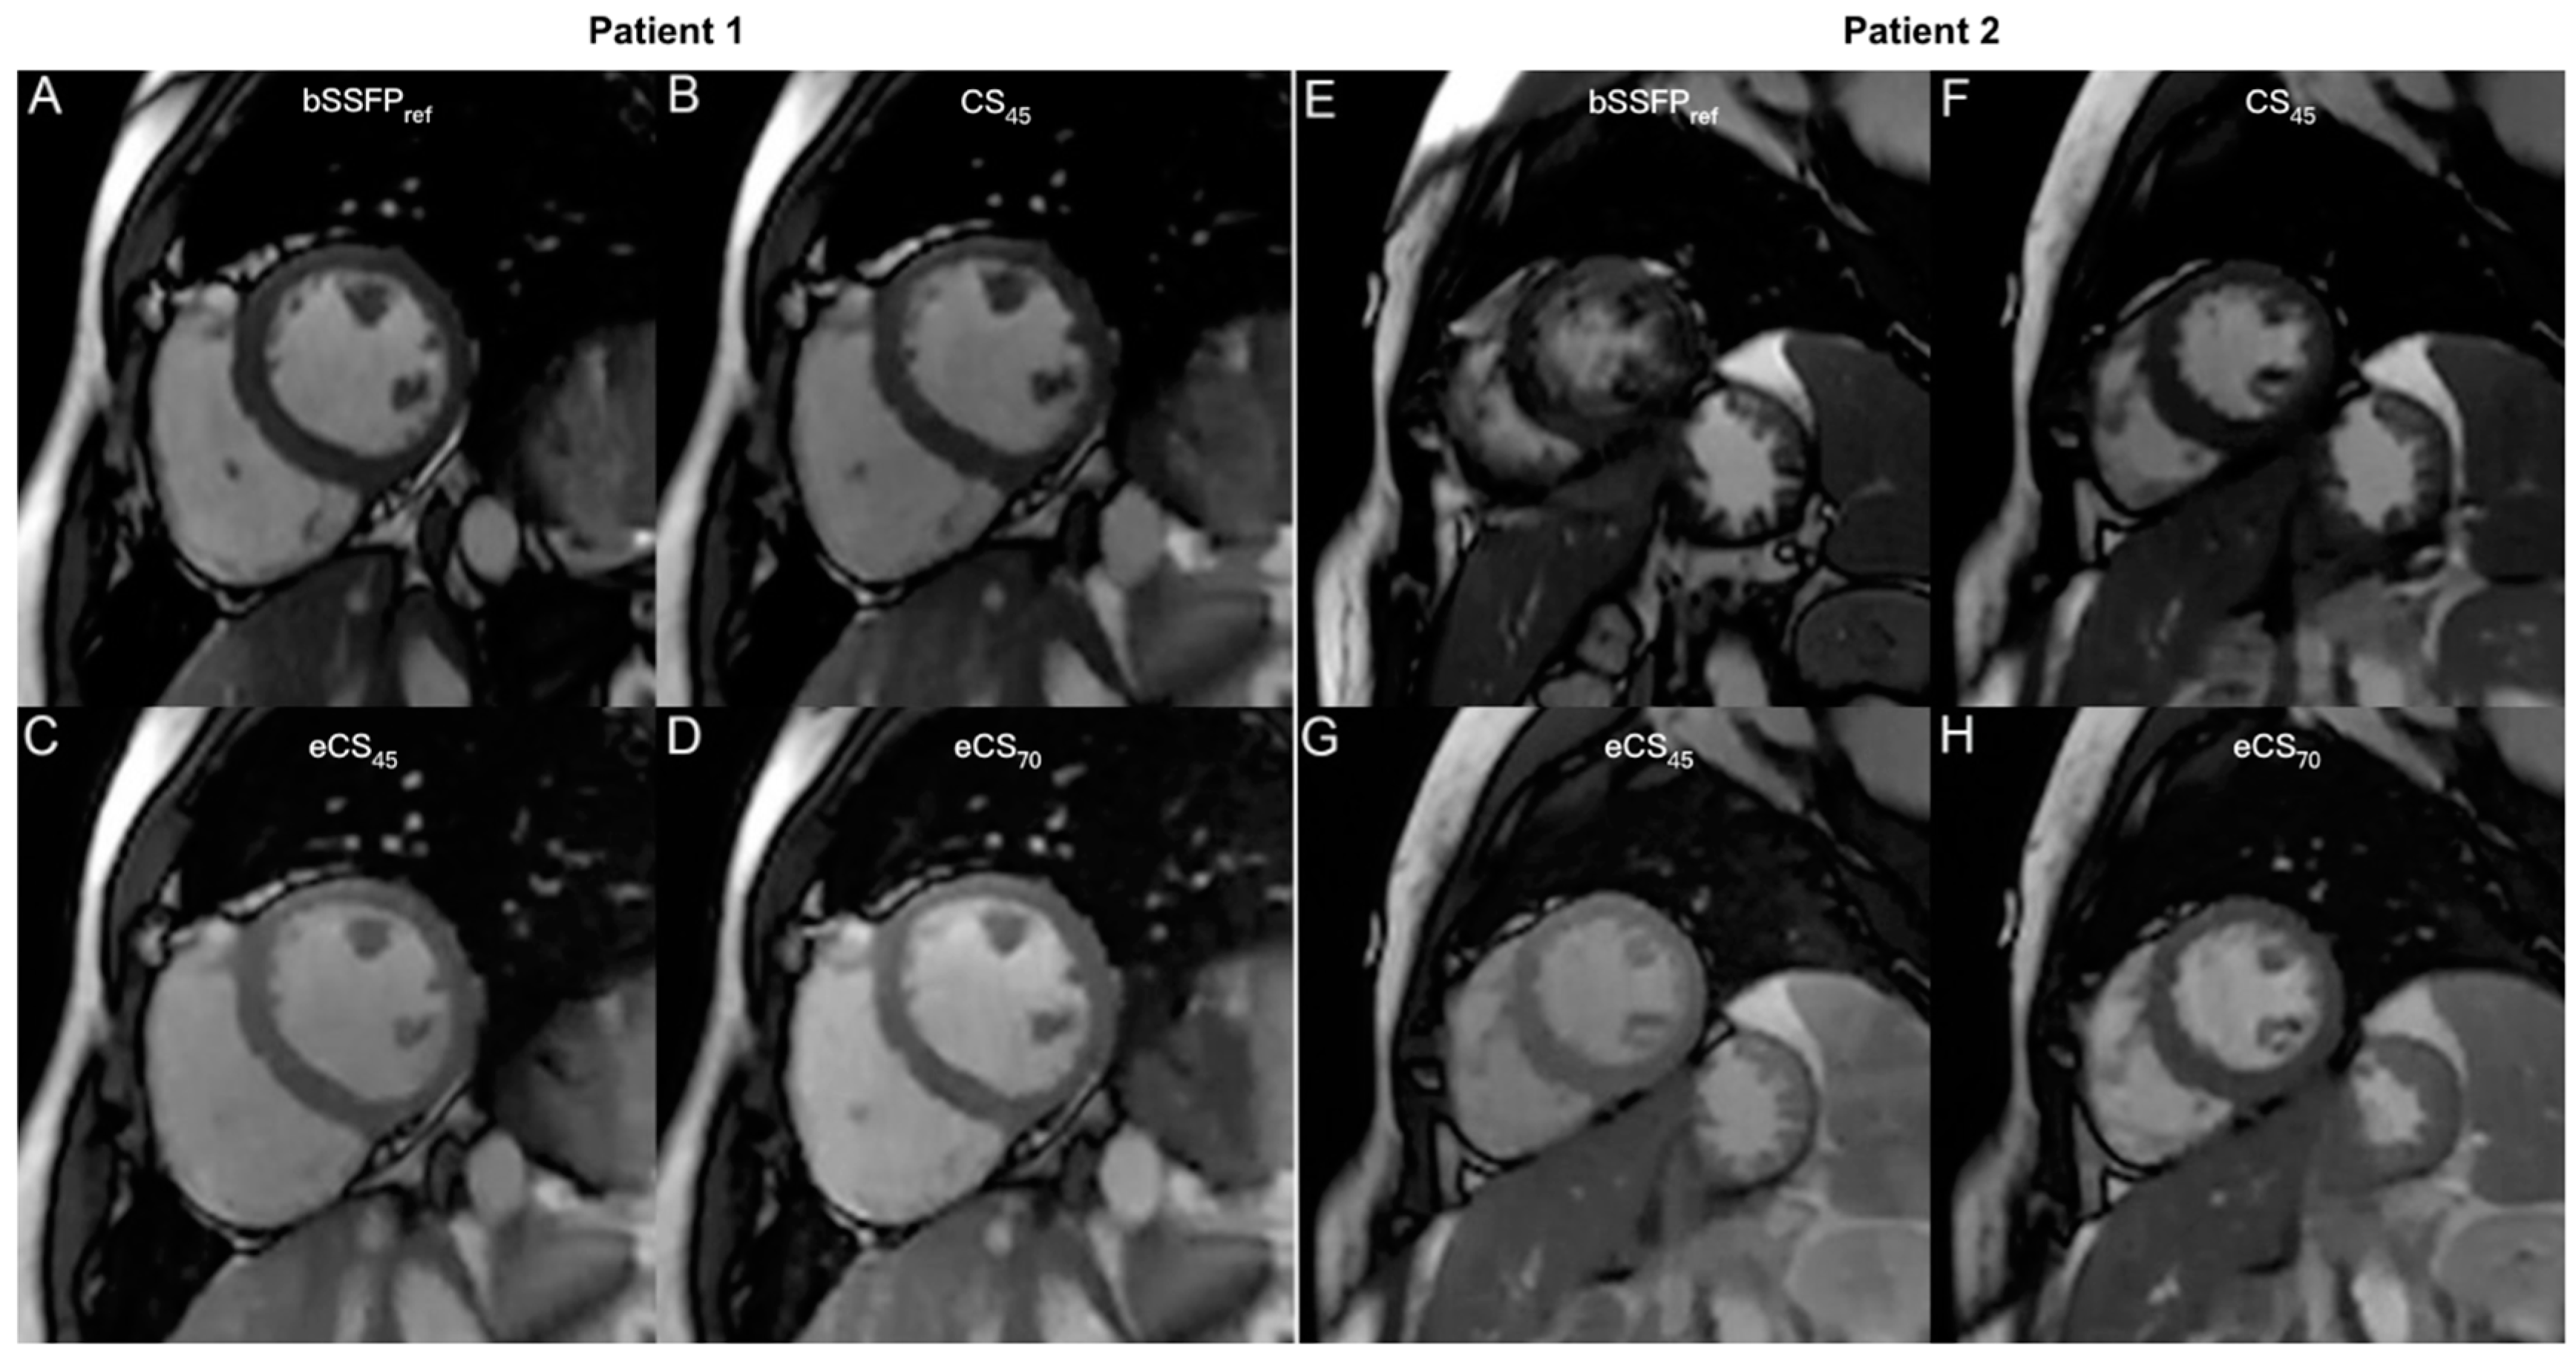

3.3. Image Quality